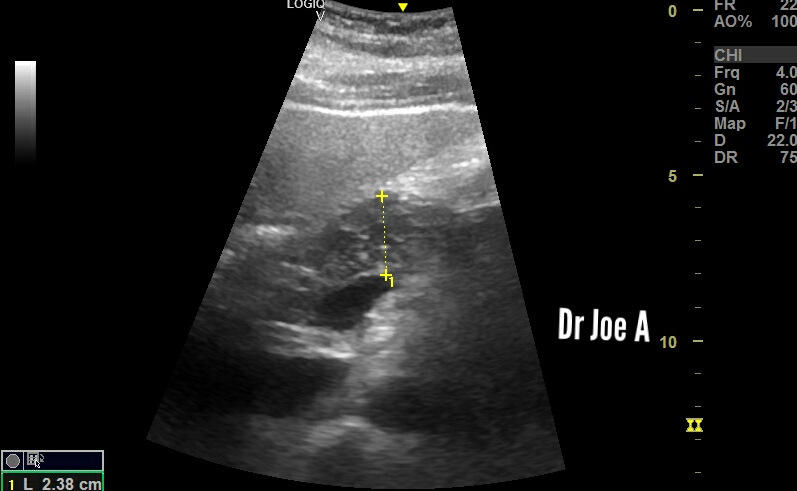

A cyst in epigastric region, not vascular on color Doppler ultrasound 👆👆

Is it a pancreatic pseudo cyst?

The pancreas appears normal on ultrasound 👆👆

The mysterious cyst is 2.5 cms in size.

Final diagnosis: mesenteric cyst

Advised CT scan confirmation 👍.